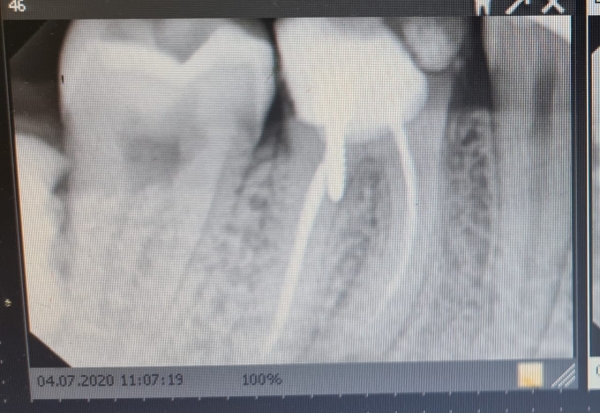

Штифт стоит крайне некорректно, а правильнее сказать в зубе имеется перфорация, и данный зуб подлежит удалению в ближайшее время.

А для того, чтобы установить коронку необходимо восстановить культевую часть зуба, в вашем случае только вкладкой, и для этого необходимо удалить штифт.